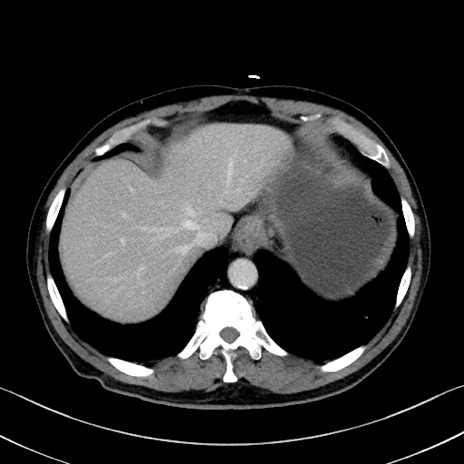

症例35(横断像)

【症例】70歳代 男性

【主訴】腹部膨満、嘔吐

【現病歴】昨日より腹部膨満感出現。本日増悪し、仙痛出現。嘔吐あり、受診。

【既往歴】糖尿病、胆摘後

【身体所見】BP 149/80mmHg、HR 74/min、BT 35.9℃、腹部:膨満、軟、圧痛なし。腸雑音減弱あり。上腹部正中切開瘢痕あり。

【データ】WBC 13500、CRP 1.72

冠状断像